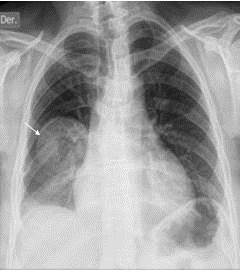

Paciente femenina de 37 años de edad, fumadora ocasional, con antecedentes de valvulopatía cardíaca corregida quirúrgicamente en la niñez, actualmente conocida sana. Acude a la consulta, por presentar cuadro clínico de un mes de evolución, caracterizado por dolor torácico tipo opresivo en región latero posterior de hemitórax derecho, con irradiación al hombro, por lo que acude a la consulta de neurocirugía, en donde es valorada diagnosticándole una dorsalgia funcional por estrés laboral por lo cual se le realiza un bloqueo analgésico intercostal sin obtener mejoría, por lo que es revalorado el caso y se plantea practicar un bloqueo radicular selectivo (BRS) con control radiológico, en quirófano con sedación consciente. Por lo que se realiza radiografía de tórax póstero-anterior donde se observa un patrón de masa tumoral localizada en el centro del pulmón derecho y se extienden periféricamente, homogénea de bordes bien definidos, con distribución lobar (lóbulo inferior derecho) sub-pleural, asociada a la pérdida de volumen (Figura 5). Motivo por el cual es referida a la consulta de cirugía de tórax, en donde es valorada. La paciente luce en buenas condiciones generales hemodinámicamente estable. A la exploración física; tórax simétrico con buenas expansibilidad respiratoria, eupneica, a la auscultación se apreció disminución del murmullo vesicular, con roncus y crepitantes basales a nivel del campo pulmonar derecho, el resto de la exploración clínica sin alteraciones.

En vista del hallazgo radiológico y clínico, se procede a realizar TAC de tórax para completar el estudio de la paciente, con tomógrafo BRIGHT SPEED® de 16 detectores sin la administración de contraste intravenoso. Se evidencia imagen de masa con márgenes bien definidos con morfología redondeada, que mide entre 9 cm x 7 cm, con valores de atenuación entre 23-43 UH, isodensa homogénea, contornos suaves en contacto con pared torácica y sub-pleural. Ausencia de adenopatías de la cadena mediastinal, supra-carinalis y perihiliar (Figura 6).